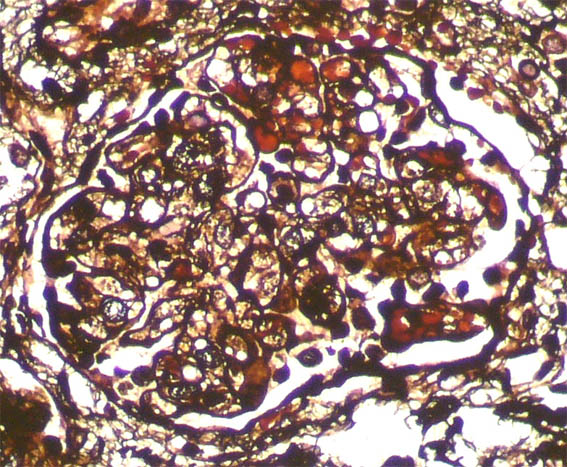

Se hace biopsia renal. Observe las imágenes.

Plata-metenamina, X400.

Figura 9. Plata-metenamina, X400.